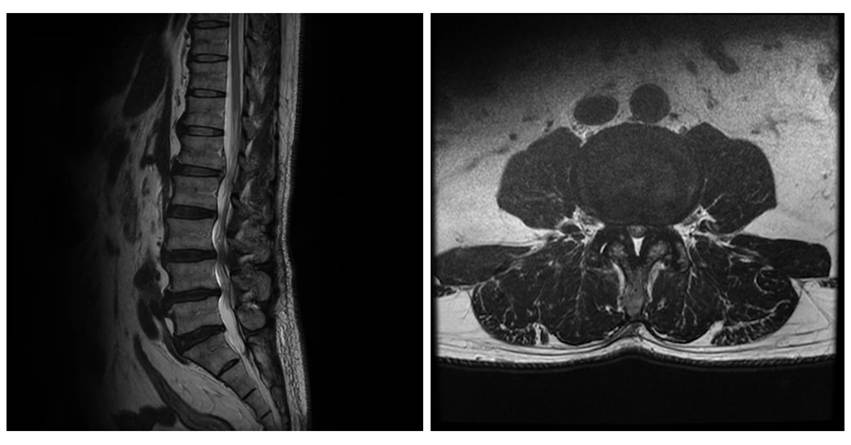

脊柱管狭窄症とは、背骨の中にある神経の通り道(=脊柱管)が狭くなった状態です。

脊柱管の狭窄は、脊椎のどの部分にも起こり得ますが、最も発症頻度が高いのは腰(腰部脊柱管狭窄症)と、首(頸部脊柱管狭窄症)です。いずれも50歳以上によく発生するもので、男性に多い傾向があります。